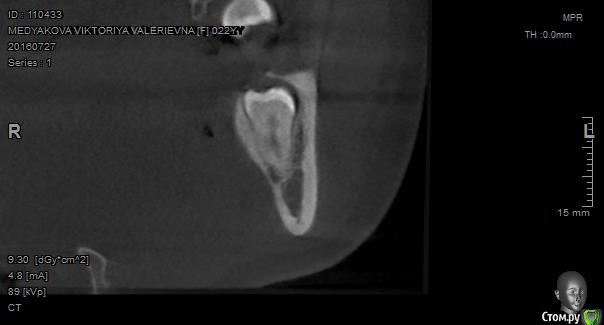

Павел7809 Опубликовано 22 сентября, 2016 Поделиться Опубликовано 22 сентября, 2016 Мои 5 копеек. Выглядит не страшно но любовь зуба с нижничелюстным нервов пощекотала нервы...попозже выложу срезы кт Ссылка на комментарий